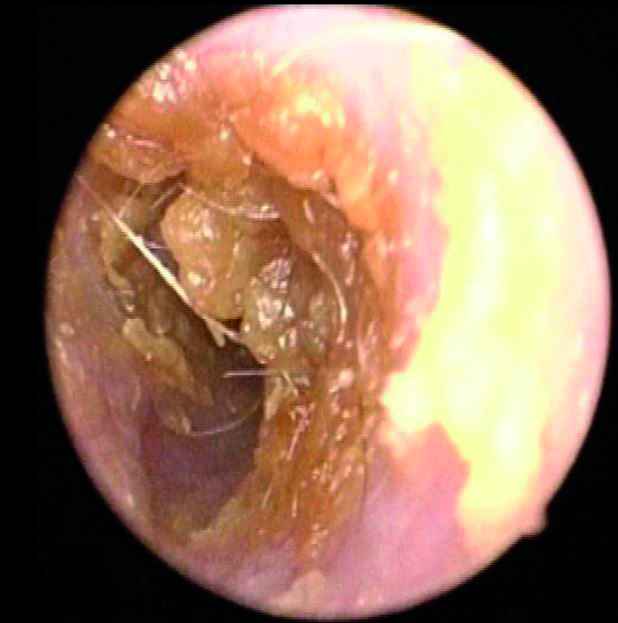

Mercredi 12 Mars 2025 Animaux de compagniePhoto n° 1 : Cérumen jaunâtre abondant obstruant partiellement le MAE visualisé en vidéo-otoscopie.